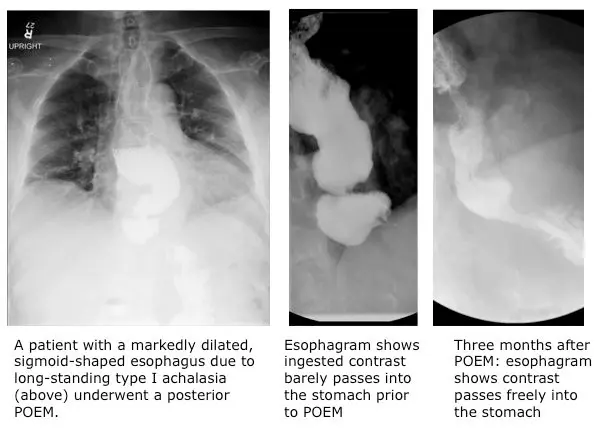

Achalasia is the result of idiopathic nerve damage that impairs the function and coordination of the muscular wall of the esophagus and impedes the lower esophageal sphincter from opening into the stomach. The result is an accumulation of food and liquid in the esophagus, which can cause a feeling of something being stuck in the chest, as well as chest pain after eating, regurgitation and even pneumonia. A progressive, incurable condition that occurs primarily in patients between the ages of 30 and 60, achalasia may eventually lead to severe swelling of the esophagus (a mega-esophagus), and often results in weight loss and malnutrition.

Not all patients are suitable candidates for POEM, so an accurate diagnosis is critical. At UVA Health System, patients experiencing dysphasia undergo a comprehensive evaluation and multiple diagnostic tests. An esophagram and/or esophageal manometry, in addition to a physical exam, can diagnose achalasia and rule out other conditions that cause dysphasia (such as cancer or neurological disorders). High-resolution esophageal manometry, which is offered at UVA, can also determine the specific subtype of achalasia, allowing doctors to choose the best treatment option for each individual patient.

The POEM procedure may be especially beneficial for patients diagnosed with type III achalasia, which is a variant that is more difficult to treat. Additionally, POEM can be done as a salvage procedure after Heller myotomy in those with a poor clinical response.